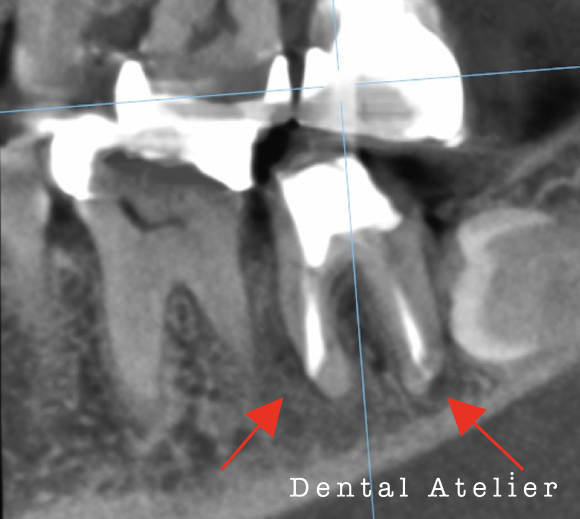

根の先の膿を診断され、治療を「抜歯」と言われた患者さんが来院されました。

当院にて、マイクロスコープ下で自費の精密根管治療を行いました。

MTAセメントにて根管充填を行い、5か月後のCT写真です。

初診時

5か月後

初診時、矢印の先にあった黒い影(膿の袋)が5か月後には無くなり、溶けた骨が再生してきています。

完全に骨化するには半年以上かかる見込みです。